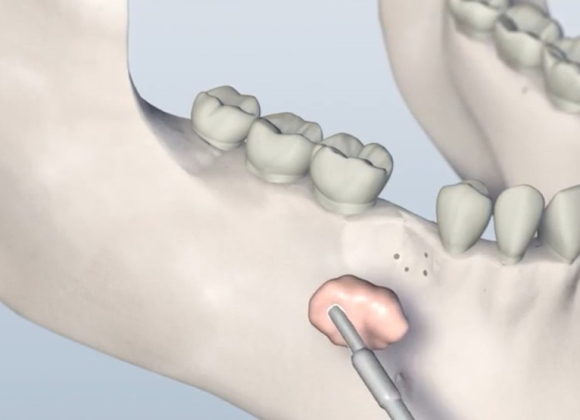

Minor grafting procedures are often performed in preparation for dental implants, especially when the bone is too thin or soft to support an implant securely. These procedures are typically done in-office under local anesthesia or IV sedation.

• Socket preservation (graft placed immediately after a tooth extraction)

• Ridge augmentation (to rebuild natural contours of the jawbone)

• Guided bone regeneration (GBR) using specialized membranes to support healing and bone regrowth

These techniques improve bone volume and quality, creating the ideal conditions for successful implant placement.